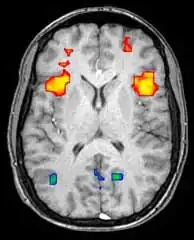

Functional magnetic resonance imaging (fMRI) and arterial spin labeling (ASL) relies on the paramagnetic properties of oxygenated and deoxygenated hemoglobin to see images of changing blood flow in the brain associated with neural activity. This allows images to be generated that reflect which brain structures are activated (and how) during the performance of different tasks or at resting state. According to the oxygenation hypothesis, changes in oxygen usage in regional cerebral blood flow during cognitive or behavioral activity can be associated with the regional neurons as being directly related to the cognitive or behavioral tasks being attended.

Most fMRI scanners allow subjects to be presented with different visual images, sounds and touch stimuli, and to make different actions such as pressing a button or moving a joystick. Consequently, fMRI can be used to reveal brain structures and processes associated with perception, thought and action. The resolution of fMRI is about 2-3 millimeters at present, limited by the spatial spread of the hemodynamic response to neural activity. It has largely superseded PET for the study of brain activation patterns. PET, however, retains the significant advantage of being able to identify specific brain receptors (or transporters) associated with particular neurotransmitters through its ability to image radiolabeled receptor "ligands" (receptor ligands are any chemicals that stick to receptors). There is also significant concern regarding the validity of some of the statistics used in fMRI analyses; hence, the validity of conclusions drawn from many fMRI studies.[22]